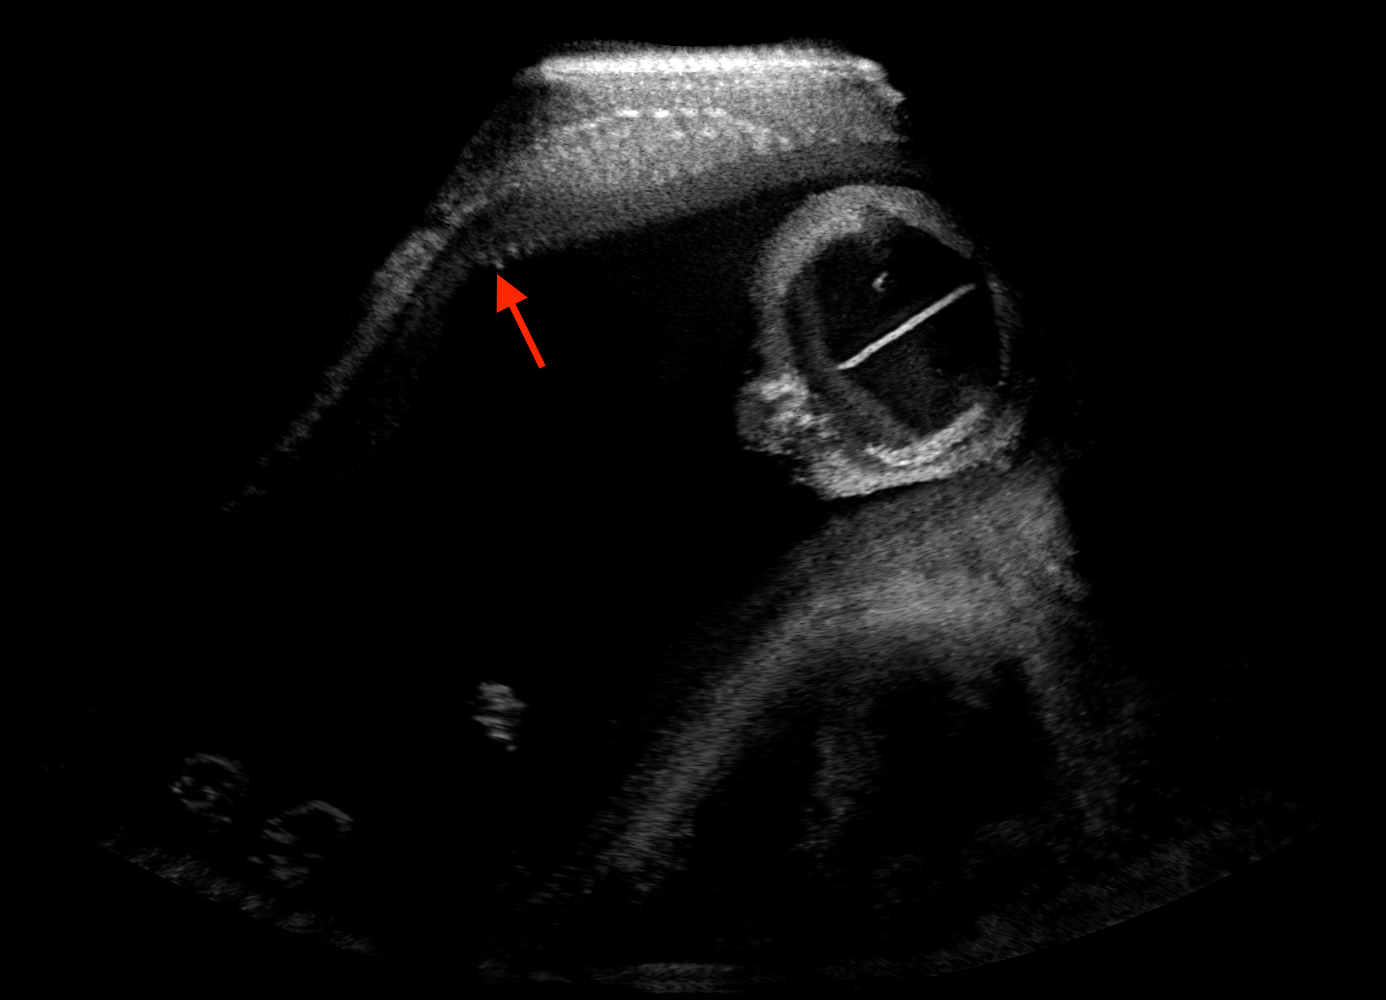

Qualitative evaluation.

Fig. 2 depicts the qualitative results for all the models mentioned above, with arrows pointing at structures relevant to discussion points below. The visual results of the ablated variants of SA2H show substantial quality degradation compared to the full SA2H model, demonstrating the importance of each proposed architectural contribution. Given only segmentation map in the network input, SA2H-att fails to generate acoustic shadows, e.g. those cast by the ribs. Detailed structures such as the cervical vertebrae are blurred out in the SA2H-concat results, which also contain hallucinated structures mainly due to insufficient preservation of input information along the encoding-decoding path. With SA2H-conv, checkerboard artefacts are observed due to the lack of proposed additional stride-1 convolutional layers. SA2H-noise without any explicit noise input is seen to be sub-optimal at generating textural details. The baseline method NSA2H fails to preserve anatomical structures and acoustic shadows in all cases, while the simulated textures also show significant artefacts such as checkerboard patterns. Realism of different simulation aspects may become relevant given different clinical applications and scenarios. For instance, improved structural preservation, e.g. with the hyperechoic bony structures such as the skull and the ribs, of the final model over its ablated variants and NSA2H may prove relevant in fetal head measurements, while the textural improvements facilitating screening fetal organ maturity, e.g. lungs. Compared to the silver-standard model LSA2H with a low-quality rendered image as additional input, SA2H is seen to be on par in structural preservation. Note that shadowing on homogenous regions (e.g. the rib shadowing on the homogenous lung region on the 4th column of Fig. 2) with our proposed method SA2H is represented more faithfully compared to LSA2H, whereas shadows on structurally complex regions (e.g. the skull shadowing around the heart and surrounding tissues on the 3rd column of Fig. 2) are suboptimal with our SA2H. Therefore, one may have to evaluate our method given particular simulation tasks, e.g. its clinical validity for fetal heart exams. However, even with low quality rendered images, LSA2H leads to artificial enhancements of intensities, lack of acoustic shadows, and low-quality textures especially near the probe, for which SA2H yields satisfactory results as illustrated in Fig. 2.

For the interpretation of the local errors, sample spatial p error maps are depicted in Fig. 3 for LSA2H, NSA2H, and SA2H for the middle two examples shown in Fig. 2. Both images generated by NSA2H have a lot of missing structures and accordingly have high error almost all over the map. Artificial skull enhancement with LSA2H is seem to evoke large p error, as shown in the corresponding error map, whereas the bright spots in the error map of SA2H reflect some hallucinated shadows and structure in the brain. All of above mentioned regions of interest are marked by red arrows. In the bottom example, SA2H fails to generate faithful content at the bottom region marked by red circles, which is well indicated by the error map as well.